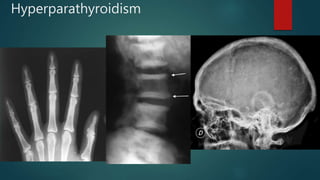

Hyperparathyroidism

•HAM HOP

Mnemonic

•H: hyperparathyroidism

•A: (renal tubular) acidosis

•M: medullary sponge kidney

•H: hypercalcaemia/hypercalciuria

•O: oxalosis

•P: papillary necrosis